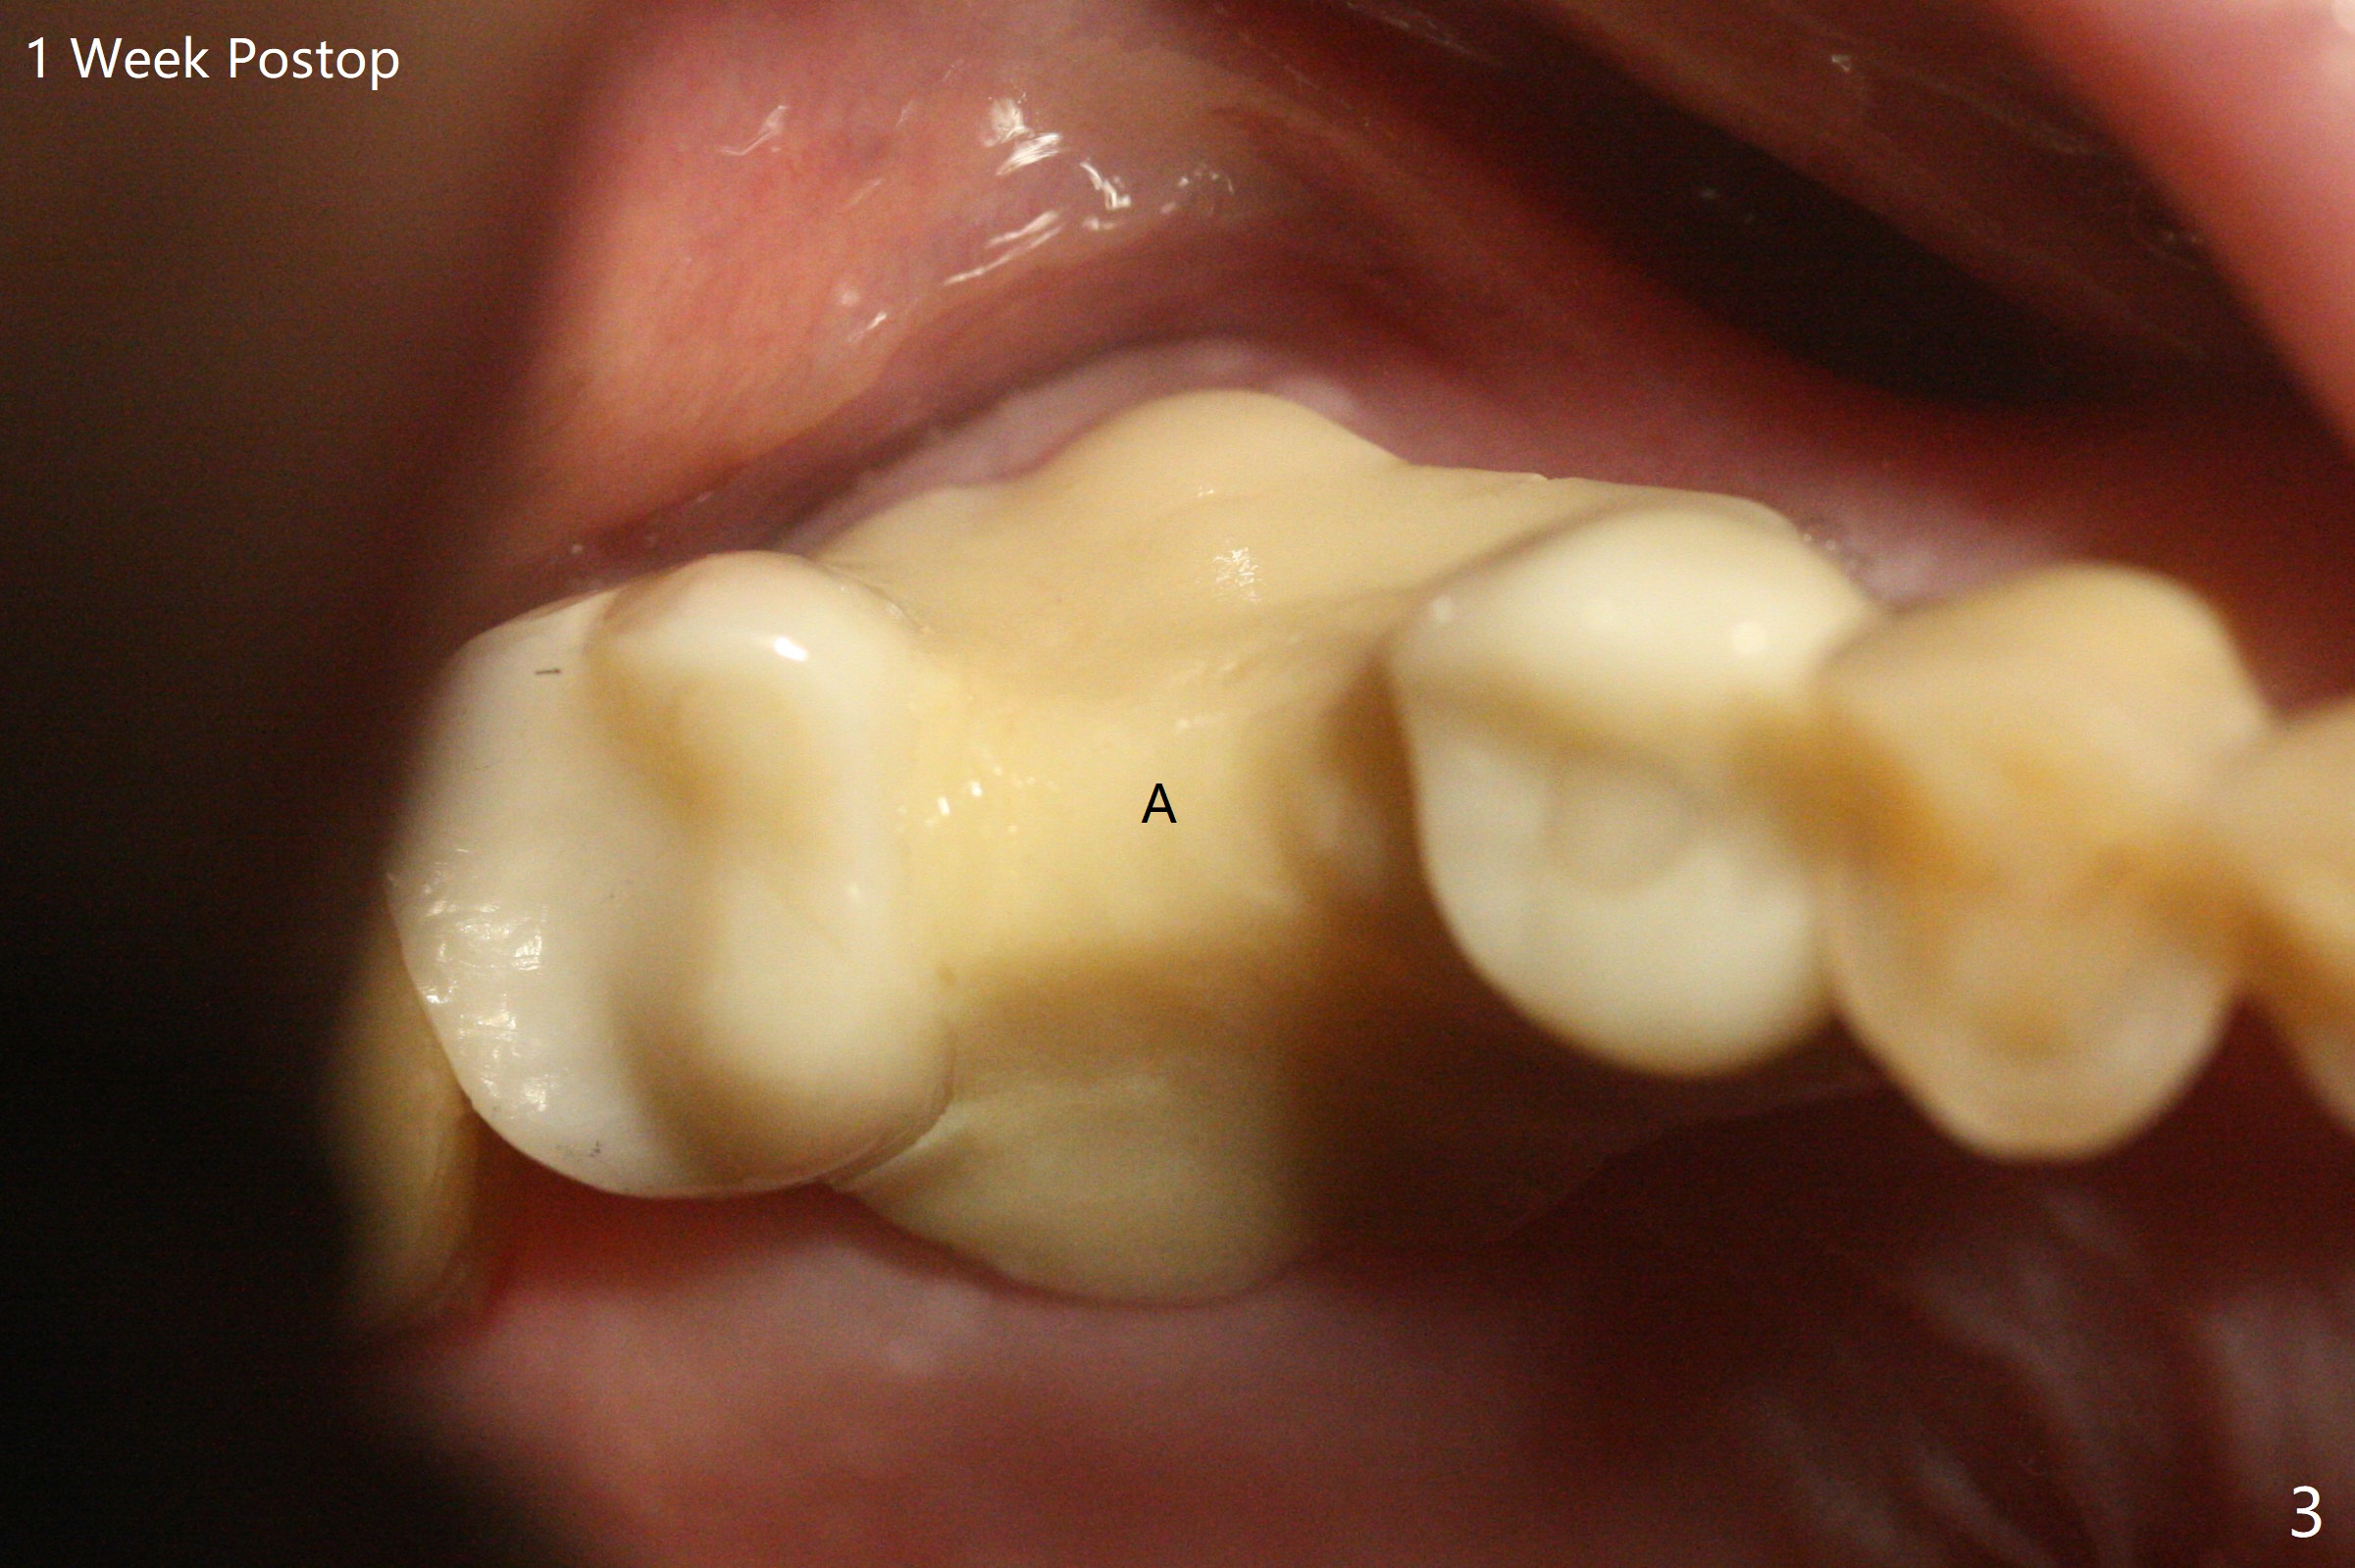

51岁男(牙周炎,咀嚼力大),右上6植体(7x17毫米,即刻种植,当时牙槽窝大,使用大植体,减少骨粉量)使用6年10月后松动,在诊所用手指取出,颊侧牙龈低,刮拔肉芽组织时发现颊侧,腭侧骨壁都缺失,但是没有通入上颌窦,植入粘性骨粉(Vanilla),覆盖一张PRF膜,4-0PGA缝线尽量严密缝合(图一,让口子骨粉有充分血供,相应减少角化龈和骨质高度),然后使用树脂敷料固定(PRF膜很快吸收)。7植体近中螺纹暴露,钛刷清洗后,骨粉放置于表面,而5远中深部螺纹好像暴露,浅部却被牙龈(乳头处)覆盖,所以骨粉无法进入缺失地方(图一:*)。理想的话,应该将牙龈分离(图二:弯箭头),这样骨粉就能进入缺损区域。6愈合后植牙时,用类似方法植骨。术后一周局部卫生好,没有任何不适(图三)。当术后五周树脂敷料取出时,骨粉好像生长不好(图四)。术后两个月伤口愈合(图五),但是骨粉失去不少(图六)。Return to No Caries Xin Wei, DDS, PhD, MS 1st edition 02/09/2021, last revision 08/09/2021